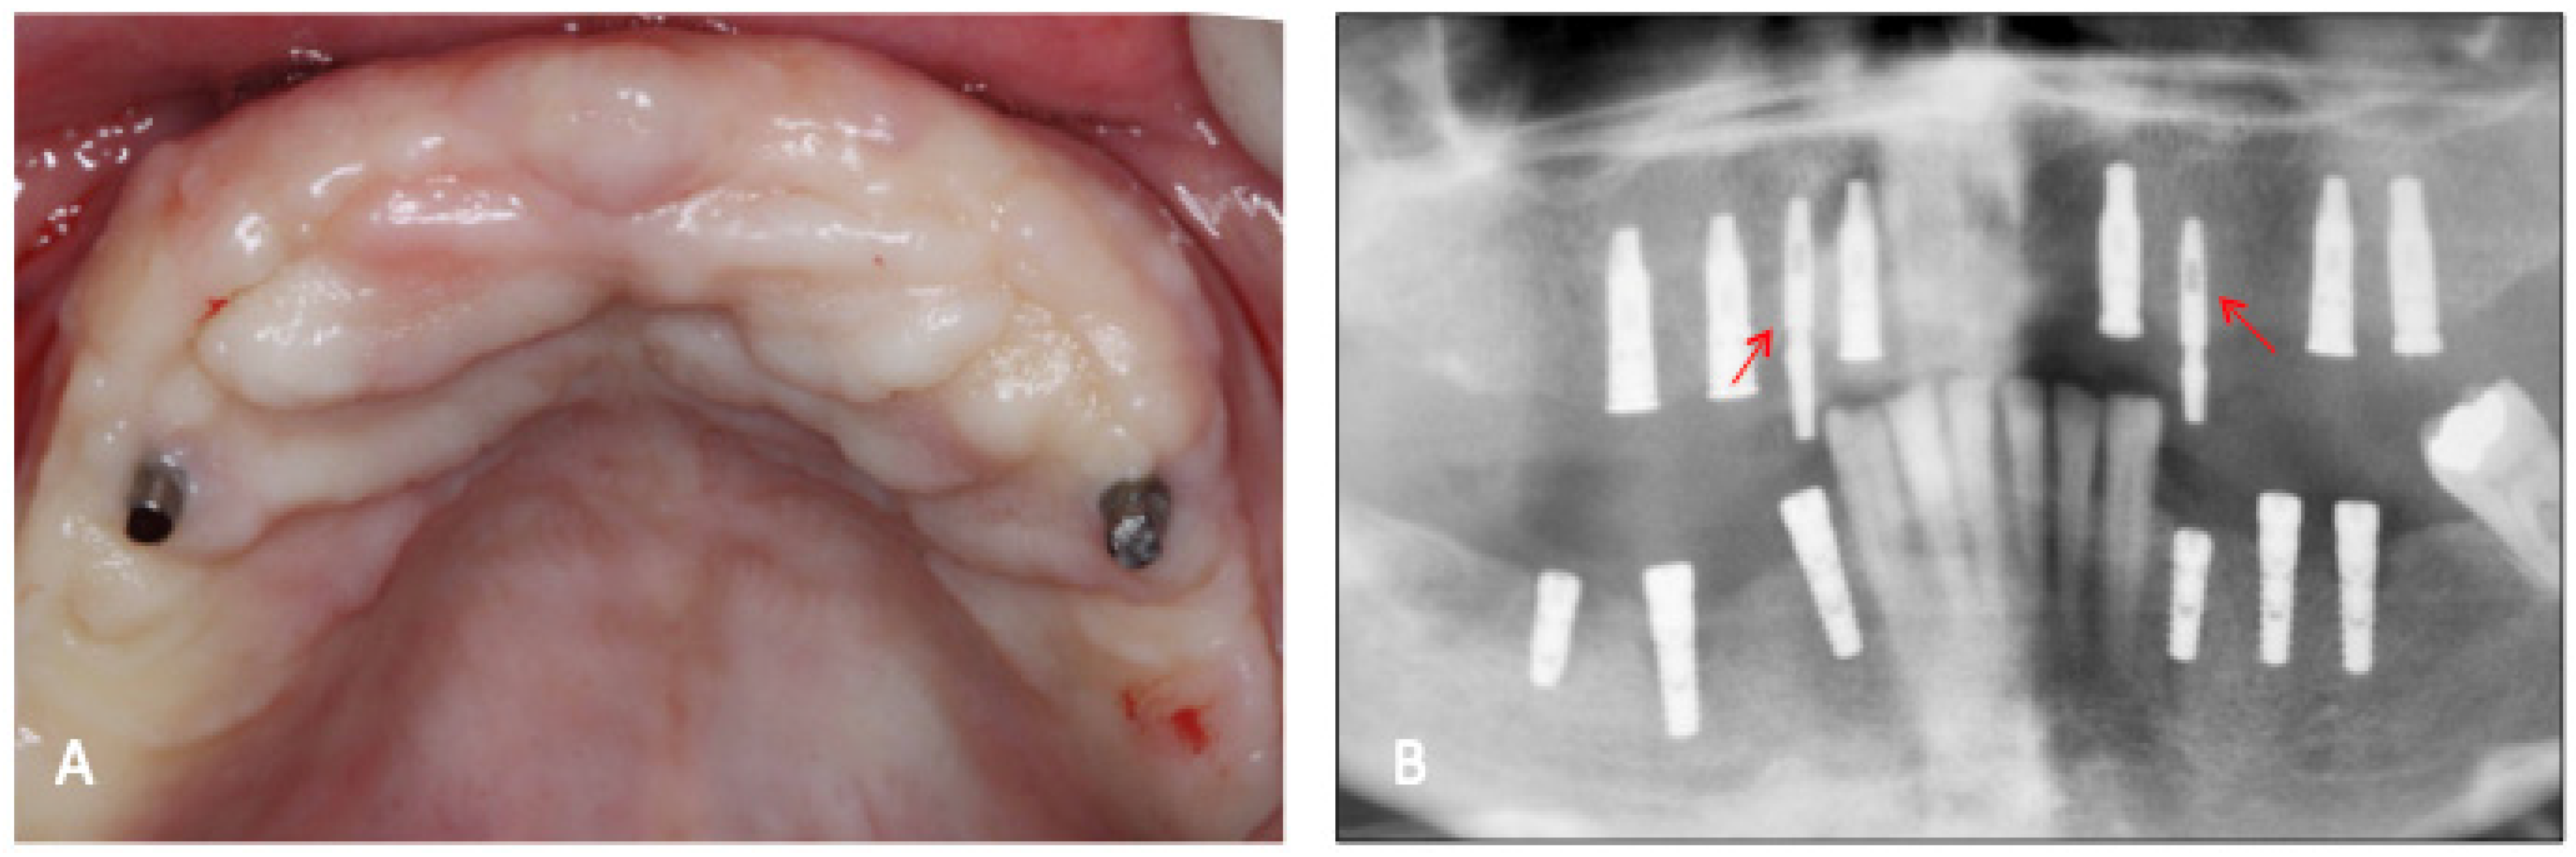

Figure 2.

(A) Clinical aspect of the temporary implants after 60 days of healing; (B) radiographic aspect of the temporary implants (arrows) and the conventional type. Note that the conventional implants were submerged and will receive the 2nd stage of surgery.